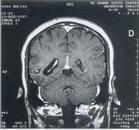

2.CT檢查 可見鈣化和單側腦萎縮。

3.MRI PET和SPECT 可顯示軟腦膜血管瘤。

斯特奇-韋伯綜合症 CT掃描1.影像學檢查頭顱X線平片可顯示顱內鈣化影,呈腦回狀、線狀、樹枝狀、雙軌狀,其中與腦表面外形一致的雙軌狀是特徵性改變。顱內鈣化影可見於大腦各葉皮質,20歲以後的患者多見,發生率為50%~87.2%。多位於一側,雙側也有報導。CT平掃可見團塊狀混雜密度病灶,邊緣不清,可有鈣化影、局部腦萎縮;增強掃描可見異常血管強化影。MR成像上T1和T2加權均顯示低信號影,對鈣化的顯示不如CT掃描。數字減影血管造影(DSA)有助於腦部畸形血管的定性、定位。